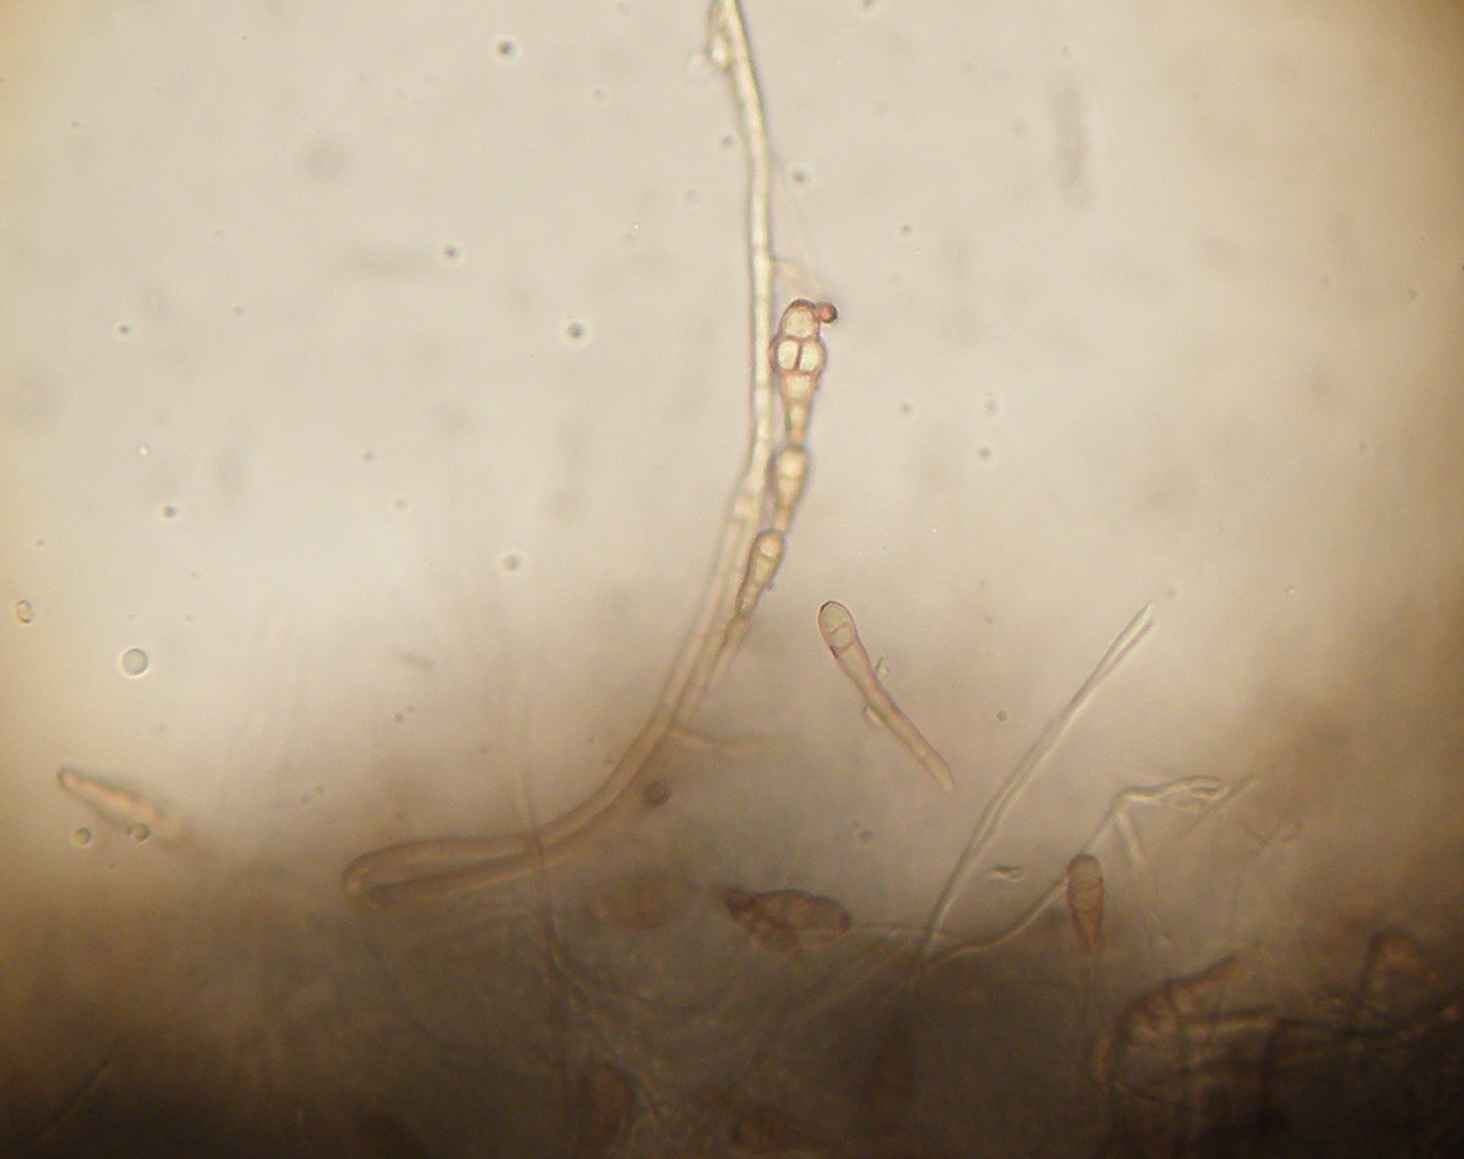

A estirpe isolada revelou na análise microscópica uma intensa e típica esporulação.

Cadeias de conideos multicelulares típicas. As cadeias podem ser simples ou ramificadas.

Hifas com pigmento castanho.

A alternaria alternata perde frequentemente a capacidade de esporular em cultura tornando difícil a identificação do isolado se não houver histórico no laboratório para o paciente em causa. A exposição aos raio UV pode estimular a esporulação.